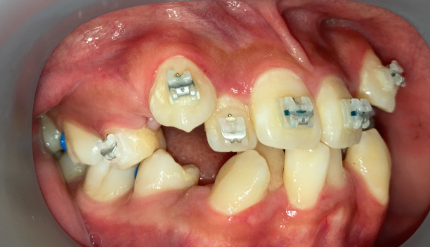

非抜歯アンカー矯正の初診時|奈良の矯正歯科

初診時

インプラントアンカー装着中の矯正治療経過|奈良の矯正歯科

アンカー装着中

非抜歯アンカー矯正の治療完了|奈良の矯正歯科

治療完了

インプラントアンカーで上の歯列全体を後方に移動。抜歯せずにガタガタと口元の突出感を改善しました。